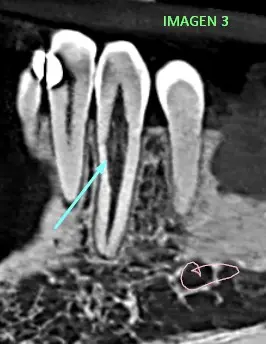

En las ilustraciones como (imagen 2 y 3) se puede observar y confirmar una reabsorción radicular interna en

pieza dentaria 33. La misma, radiograficamente se presenta por una dilatación ovalada en el interior del conducto. a diferencia de la reabsorción externa, no hay lisis del hueso vecino. Obviamente el tamaño de la lesión puede hacerla externa, como se cree en este caso, donde se observa la normalidad de la cresta alveolar vecina.